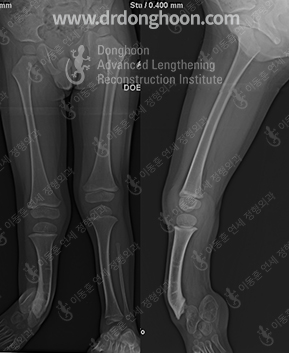

Среди трудноизлечимых болезней опорно-двигательного аппарата есть много болезней, нуждающихся в удлинении костей или коррекции деформации костей. Всемирный лидер по удлинению и коррекции деформации костей, научный ортопедический центр доктора Ли Донгхуна постоянно ведет исследования по трудноизлечимым болезням опорно-двигательного аппарата, чтобы помочь во всем мире людям, страдающим этими болезнями.